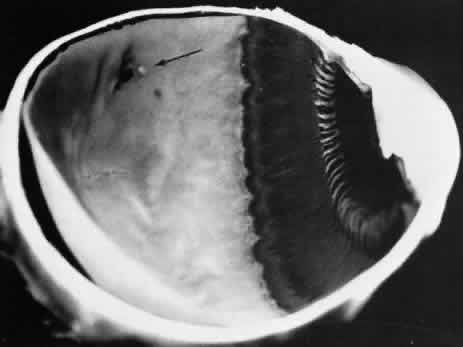

DEGENERATIVE RETINOSCHISIS

Degenerative retinoschisis, a more extensive trophic process, presents as a round or ovoid area of retinal splitting with a smooth fusiform elevation of the inner layer (Fig. 17). The schisis is surrounded on all sides by typical cystoid degeneration; the retinal pillars of the cystoid degeneration as well as the broken pillars near the margin of the schists are prominent. Vessels are located in the inner retinal layer, the intraretinal cavity is optically empty, and the outer retinal layer is moderately irregular in contour.13,14

Fig. 17. Typical degenerative retinoschisis.Note extensive region of typical cystoid degeneration with a rounded and elevated posterior margin. In the center (arrow), radial columns are randomly disrupted, causing a disturbance in coarse surface pattern. (× 18.)

In one type of degenerative retinoschisis, the thin inner wall is composed of the internal limiting membrane, the nerve fiber layer, and retinal vessels (Fig. 18). The irregular outer wall contains portions of the inner nuclear, outer plexiform, outer nuclear, external limiting, and rod and cone layers. At the margin of the cavity, the retinoschisis blends with typical cystoid degeneration and may be relatively flat. Lesions with this appearance have been termed typical degenerative retinoschisis.

Typical degenerative retinoschisis is present in 1% of adult patients and is bilateral in 33% of these patients; therefore, it is evident in 0.7% of adult eyes (see Table 3), with a predilection for location in the inferior temporal quadrant. A narrow band of typical cystoid degeneration is always present between the ora serrata and the anterior border of the schisis cavity; the involved area may extend to or somewhat posterior to the equator.

On clinical examination, typical degenerative retinoschisis appears as round or ovoid areas of retinal splitting with fusiform elevation of the inner layer (Fig. 19). The stippled pattern of surrounding typical cystoid degeneration extends on the inner layer for a variable distance; centrally the inner layer, which contains the blood vessels, is thin and smooth. On contact lens ophthalmoscopy, the inner layer is finely textured, some of the retinal vessels are attenuated, and there is a variable number of tiny, glistening, white dot opacities on the vitreous side. The outer layer, found external to the optically empty cavity, is best seen with indirect ophthalmoscopy when it becomes white on scleral depression. It is somewhat uneven, giving an appearance of finely hammered or beaten metal. Typical degenerative retinoschisis does not extend posteriorly to threaten the macula, and it is not often associated with breaks in either retinal layer; it rarely requires treatment.

Fig. 19. Clinical appearance of typical degenerative retinoschisis: diagram of involved area and ocular fundus photographs showing optic disc, macula, and posterior portion of schisis. Within the schisis and adjacent to the margin is coarse stippling related to broken retinal pillars.